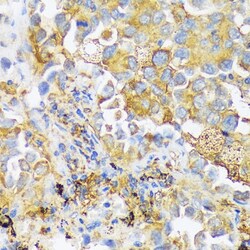

- Immunohistochemistry analysis of ZDHHC18 in paraffin-embedded human lung cancer. Samples were incubated with ZDHHC18 Polyclonal antibody (Product # PA5-116614) using a dilution of 1:100 (40x lens). Perform microwave antigen retrieval with 10 mM PBS buffer pH 7.2 before commencing with IHC staining protocol.